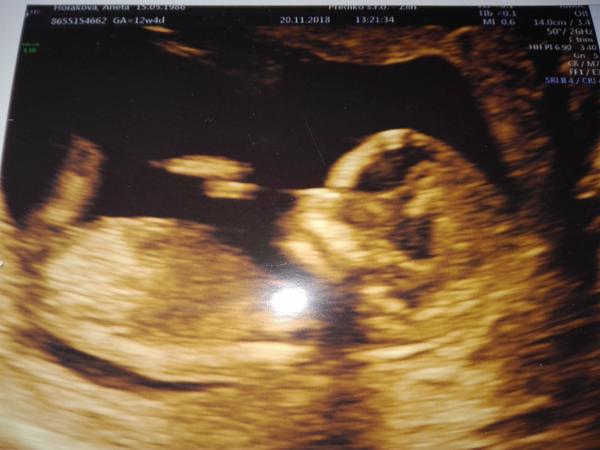

Nam to dr na druhem screeningu ukazal takto a rekl tady vidite (a ted nevim co jak jsem jiz psala ) pindika (nebo ten sourek).... Ale upa te chapu, ze to chces vedet 😃 ja byla nervozni, jestli se vbc nekdy ukaze 😃 mala se ne a ne natocit aby to slo videt, az kolem 30.tydne me rekli, ze to bude holka... Zatim (na jednu stranu) casu dost aby to slo pekne videt 🙂